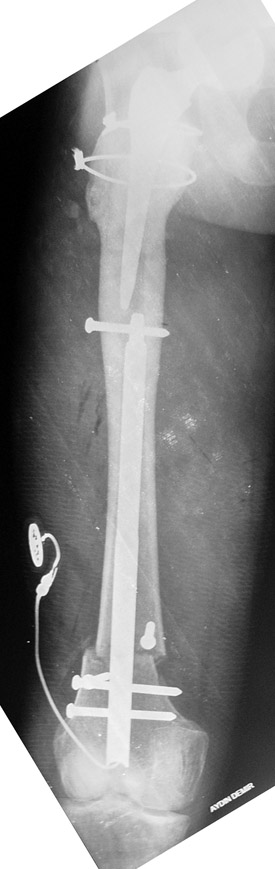

Case 1